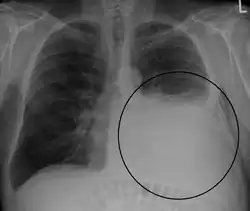

A large left-sided pleural effusion as seen on an upright chest X-ray

A pleural effusion is usually diagnosed on the basis of medical history and physical exam, and confirmed by a chest X-ray. Once accumulated fluid is more than 300 mL, there are usually detectable clinical signs, such as decreased movement of the chest on the affected side, dullness to percussion over the fluid, diminished breath sounds on the affected side, decreased vocal resonance and fremitus (though this is an inconsistent and unreliable sign), and pleural friction rub. Above the effusion, where the lung is compressed, there may be bronchial breathing sounds and egophony. A large effusion there may cause tracheal deviation away from the effusion. A systematic review (2009) published as part of the Rational Clinical Examination Series in the Journal of the American Medical Association showed that dullness to conventional percussion was most accurate for diagnosing pleural effusion (summary positive likelihood ratio, 8.7; 95% confidence interval, 2.2–33.8), while the absence of reduced tactile vocal fremitus made pleural effusion less likely (negative likelihood ratio, 0.21; 95% confidence interval, 0.12–0.37).[14]

Imaging

A pleural effusion appears as an area of whiteness on a standard posteroanterior chest X-ray.[15] Normally, the space between the visceral pleura and the parietal pleura cannot be seen. A pleural effusion infiltrates the space between these layers. Because the pleural effusion has a density similar to water, it can be seen on radiographs. Since the effusion has greater density than the rest of the lung, it gravitates towards the lower portions of the pleural cavity. The pleural effusion behaves according to basic fluid dynamics, conforming to the shape of pleural space, which is determined by the lung and chest wall. If the pleural space contains both air and fluid, then an air-fluid level that is horizontal will be present, instead of conforming to the lung space.[16] Chest radiographs in the lateral decubitus position (with the patient lying on the side of the pleural effusion) are more sensitive and can detect as little as 50 mL of fluid. Between 250 and 600mL of fluid must be present before upright chest X-rays can detect a pleural effusion (e.g., blunted costophrenic angles).[17]